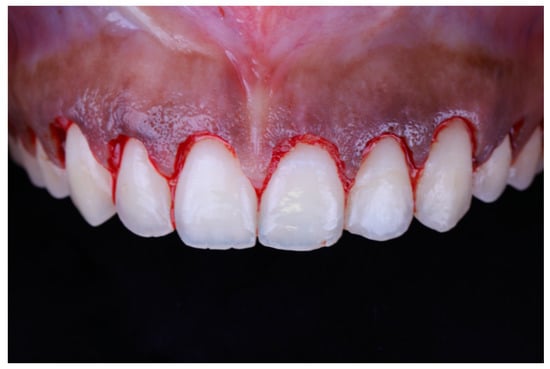

Local anesthesia (xylocaine with epinephrine 1:100.000) was administered via buccal infiltration. The guide was then placed. Using a 15c blade and following the upper border of the window of the guide, an internal bevel incision was made from right to left first molar teeth (Figure 5). The guide was then removed and a second incision was made in a sulcular fashion. The secondary flap was removed using a Youger-Good curette while visualizing the new crown lengths (Figure 6).

Figure 6.

Tooth length after gingival excision.